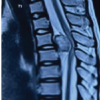

MRI revealed (Fig. 3) solitary osteochondroma of the outer margin of lower tibial metaphysis as broad stalk exostosis showing continuity of bone cortex and medullary marrow space to the host bone. This exostosis of 29 mm length and 19 × 10 mm transverse span caused extraneous chronic pressure compression and deformity of the lower fibula without any intraosseous infiltration. The tip of the lesion was surrounded by a 1 mm thin cartilaginous cap. No imaging feature for malignant transformation was reported. Extraneous compression/stretching of the peroneal vessel along with stretching of flexor hallucis longus and peroneus muscle was seen. Sheet-like soft-tissue edema of the overlying superficial subcutaneous plane was also reported.